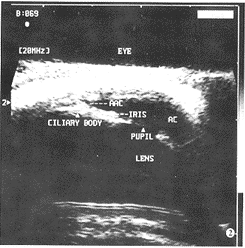

一、正常人眼前节结构的 20.0 MHz超声表现(图1,2)

图2 20.0 MHz超声示正常眼房角结构:睫状体为类似三角形高回 声,前房为无回声,前房角由角膜、角巩膜缘、巩膜、虹膜构成(AAC-前房角,CILIARY BODY- 睫状体,PUPIL-瞳孔)

5.前房角:由角膜、角巩膜缘、巩膜和虹膜构成。

7.睫状体:可清楚显示虹膜根部的睫状体,为中高回声。

8.后房:仅能观察到一个小的无回声腔隙。

角膜厚度为(0.383±0.031)mm,前房深度为(2.241±0.256)mm,晶 体厚度为(3.533±0.185)mm,虹膜厚度为(0.419±0.044)mm,睫状体厚 度为(1.131±0.094)mm。